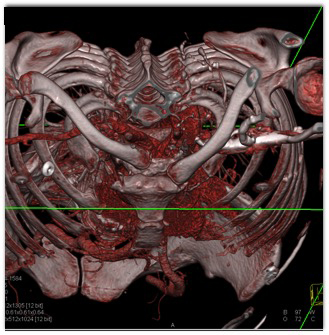

The classic dx in this patient post MVA is ?

posterior S/C dislocation